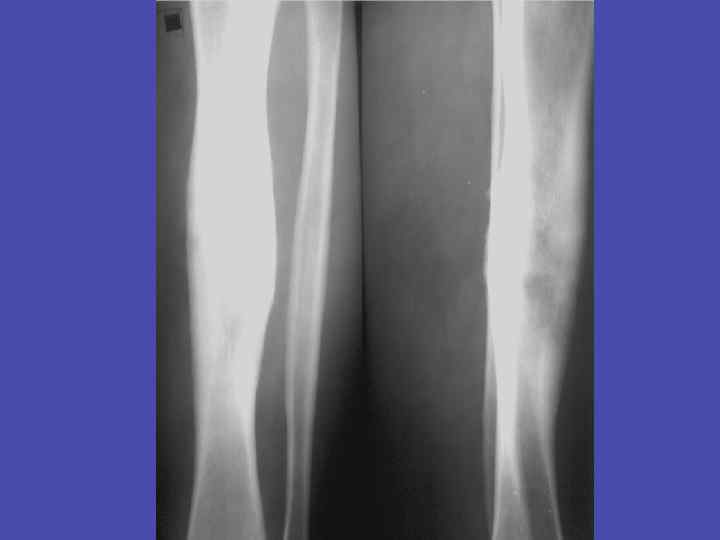

Слоистый периостит, деструкция и вырсженные репаративные процессы большеберцовой кости 38

Слоистый периостит, секвестр в секвестральной полости метадиафиза большеберцовой кости 39